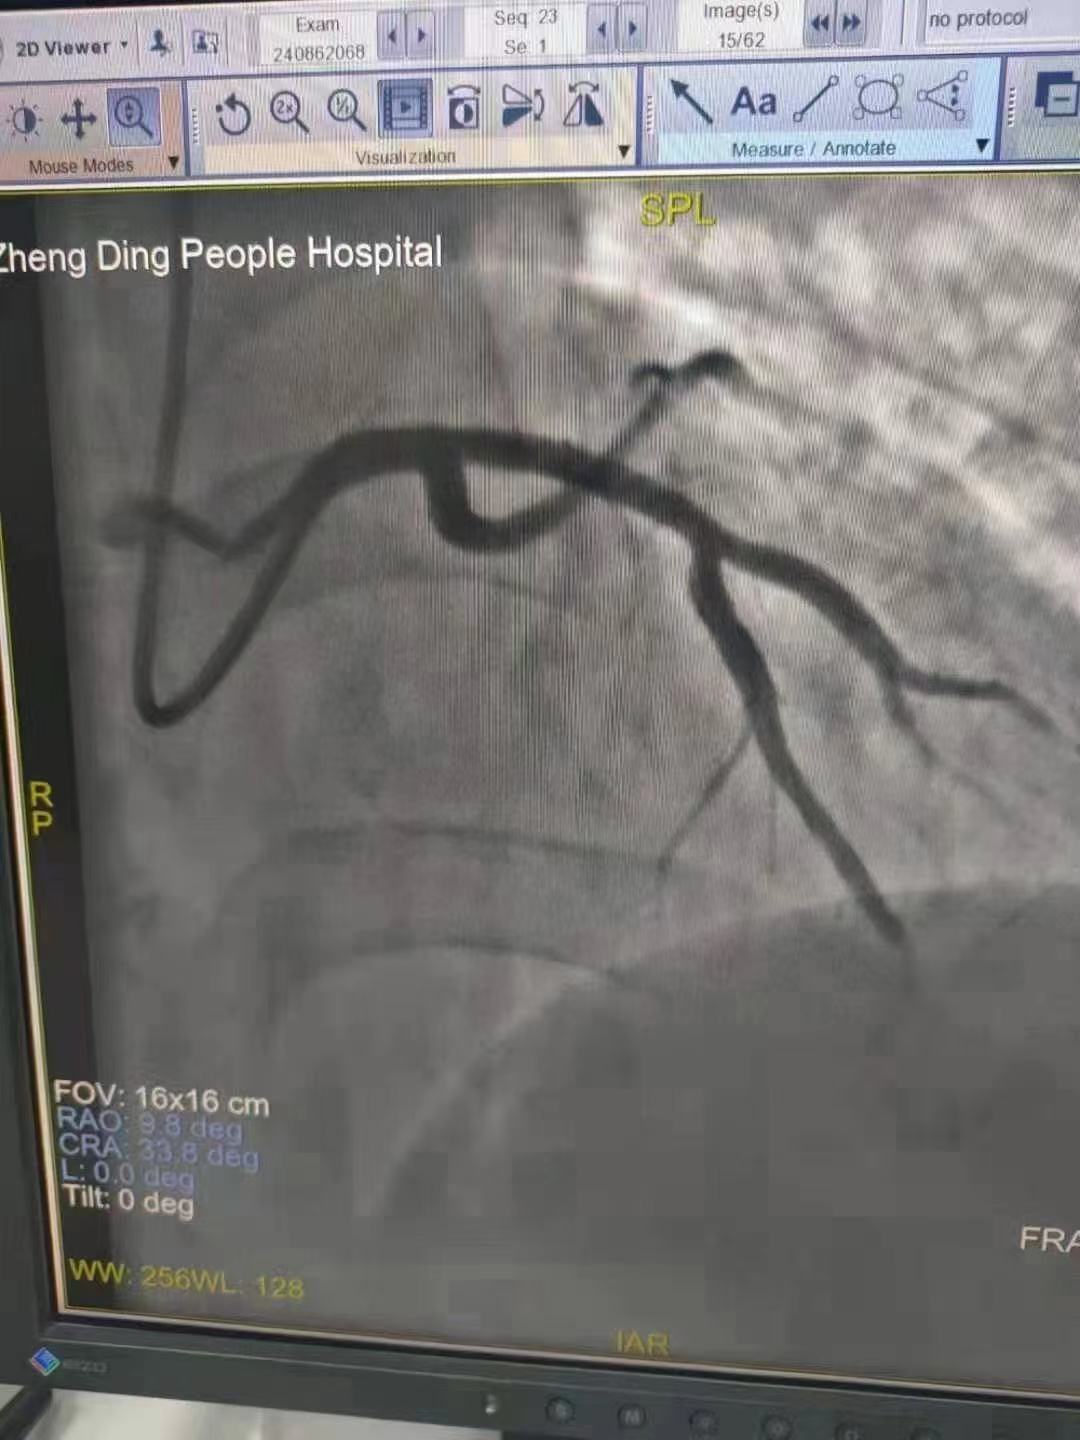

祝賀 正定縣醫(yī)院李京芳 主任團(tuán)隊成功為患者植入Xinsorb生物可吸收支架!